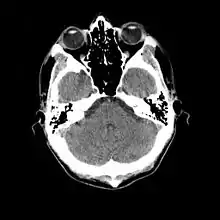

الأشعة المقطعية

الأشعة المقطعية أو التصوير المقطعى باستخدام الكمبيوتر هي تقنية تقوم على استخدام ادخال المريض داخل حلقة خاصة يوجد ترسل من أحد جهاتها الأشعة (أشعة X) ويخترق الجزء المراد تصويره في الجسم وتصل إلى مجسات (مستقبلات) خاصة في الناحية الأخرى من الحلقة ؛ وتتحرك الحلقة باستمرار مع تحرك السرير الذي ينام عليه المريض داخل الحلقة بشكل مستمر حتى نهاية الفحص، ثم يتم تحويل المعلومات إلى جهاز كمبيوتري خاص يقوم بعمل عدة حسابات معقدة ويترجمها إلى صورة أشعة على شاشة ويتم طبعا بعد ذلك عند الحاجة.

هذه التقنية تتيح الحصول على صور عالية الجودة لقطاعات عرضية من الجسم توفر معلومات طبية دقيقة. كما يمكن مع تطور الأجهزة استخدام المعلومات للحصول على صور لقطاعات طولية ورأسية مما يتيح رؤية تفاصيل أكثر وضوحا.